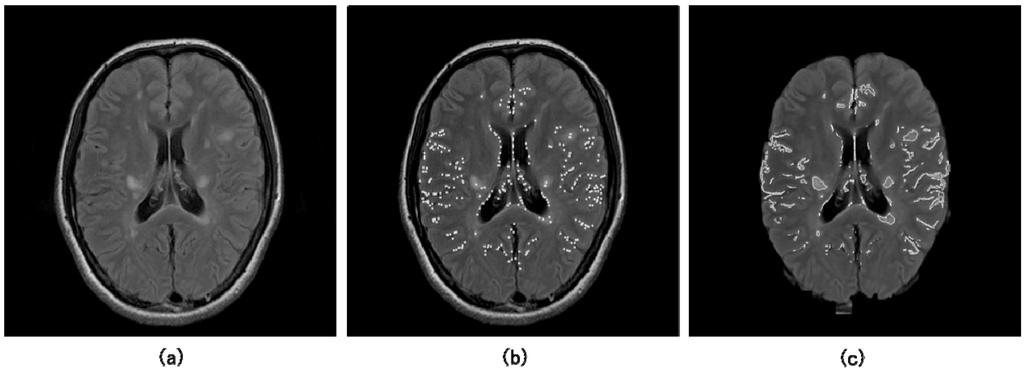

Although a number of methods for initial detection of lesions have been developed in the CAD field, basic simple thresholding techniques for outputs of enhancement filters or pixel values in the object-enhanced images have been employed for initial identification of lesions. As a unique method, Lee et al. developed an initial detection method of lung nodules using two template matching techniques based on a genetic algorithm and cross-correlation coefficient [45]. Furthermore, although it may not be directly related to the initial lesion detection, a method based on probabilistic atlases has been developed for determination of some anatomical regions such as cerebral cortical regions [46,47]. Probabilistic atlases could store information on anatomic and functional variability in a population. We have applied a multiple-gray level thresholding technique developed by Giger et al. [21,43] to the neuroradiological CAD field, for detection of initial aneurysm candidates, white matter hyperintensities (WMHs) and MS candidates in MR images as the points with local maximum pixel values in candidate regions [25,26,28,30,31]. Figure 6 shows a FLAIR image including initial MS candidate points (white dots) obtained by the multiple gray level thresholding technique, and a brain image with initial candidate regions (white solid lines) segmented by the region growing technique [30,31].

Figure 6.

Illustrations of (a) an original FLAIR image, (b) initial MS candidate points (white dots) obtained by the multiple gray level thresholding technique, and (c) initial candidate regions (white solid lines) segmented by the region growing technique [30,31].